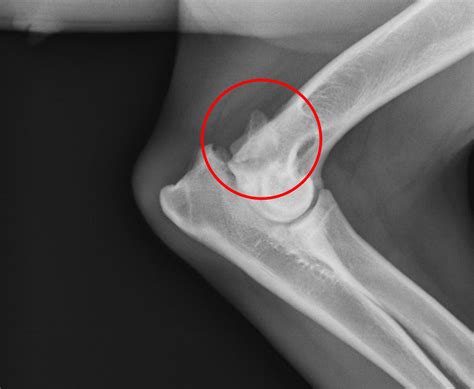

• Olecranon Fractures: Fractures of the olecranon can occur due to direct trauma, such as a fall onto an outstretched hand or a blow to the elbow. These fractures can be painful and may require surgical intervention to restore function.

• Olecranon Impingement: This condition occurs when the olecranon process rubs against the olecranon fossa of the humerus, causing pain and inflammation. It can be caused by overuse, trauma, or anatomical abnormalities.